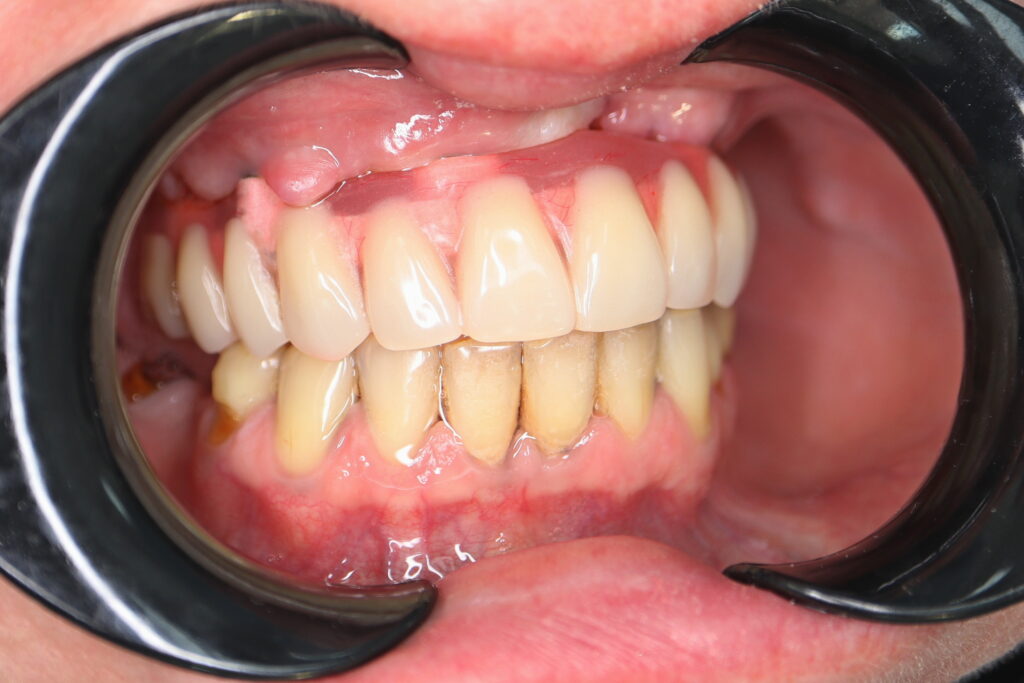

Ситуация до лечения

Жалобы: Пациент обратился с целью тотальной имплантации верхней челюсти.

Диагноз: Частичная вторичная адентия верхней челюсти.

пациент до тотальной имплантации